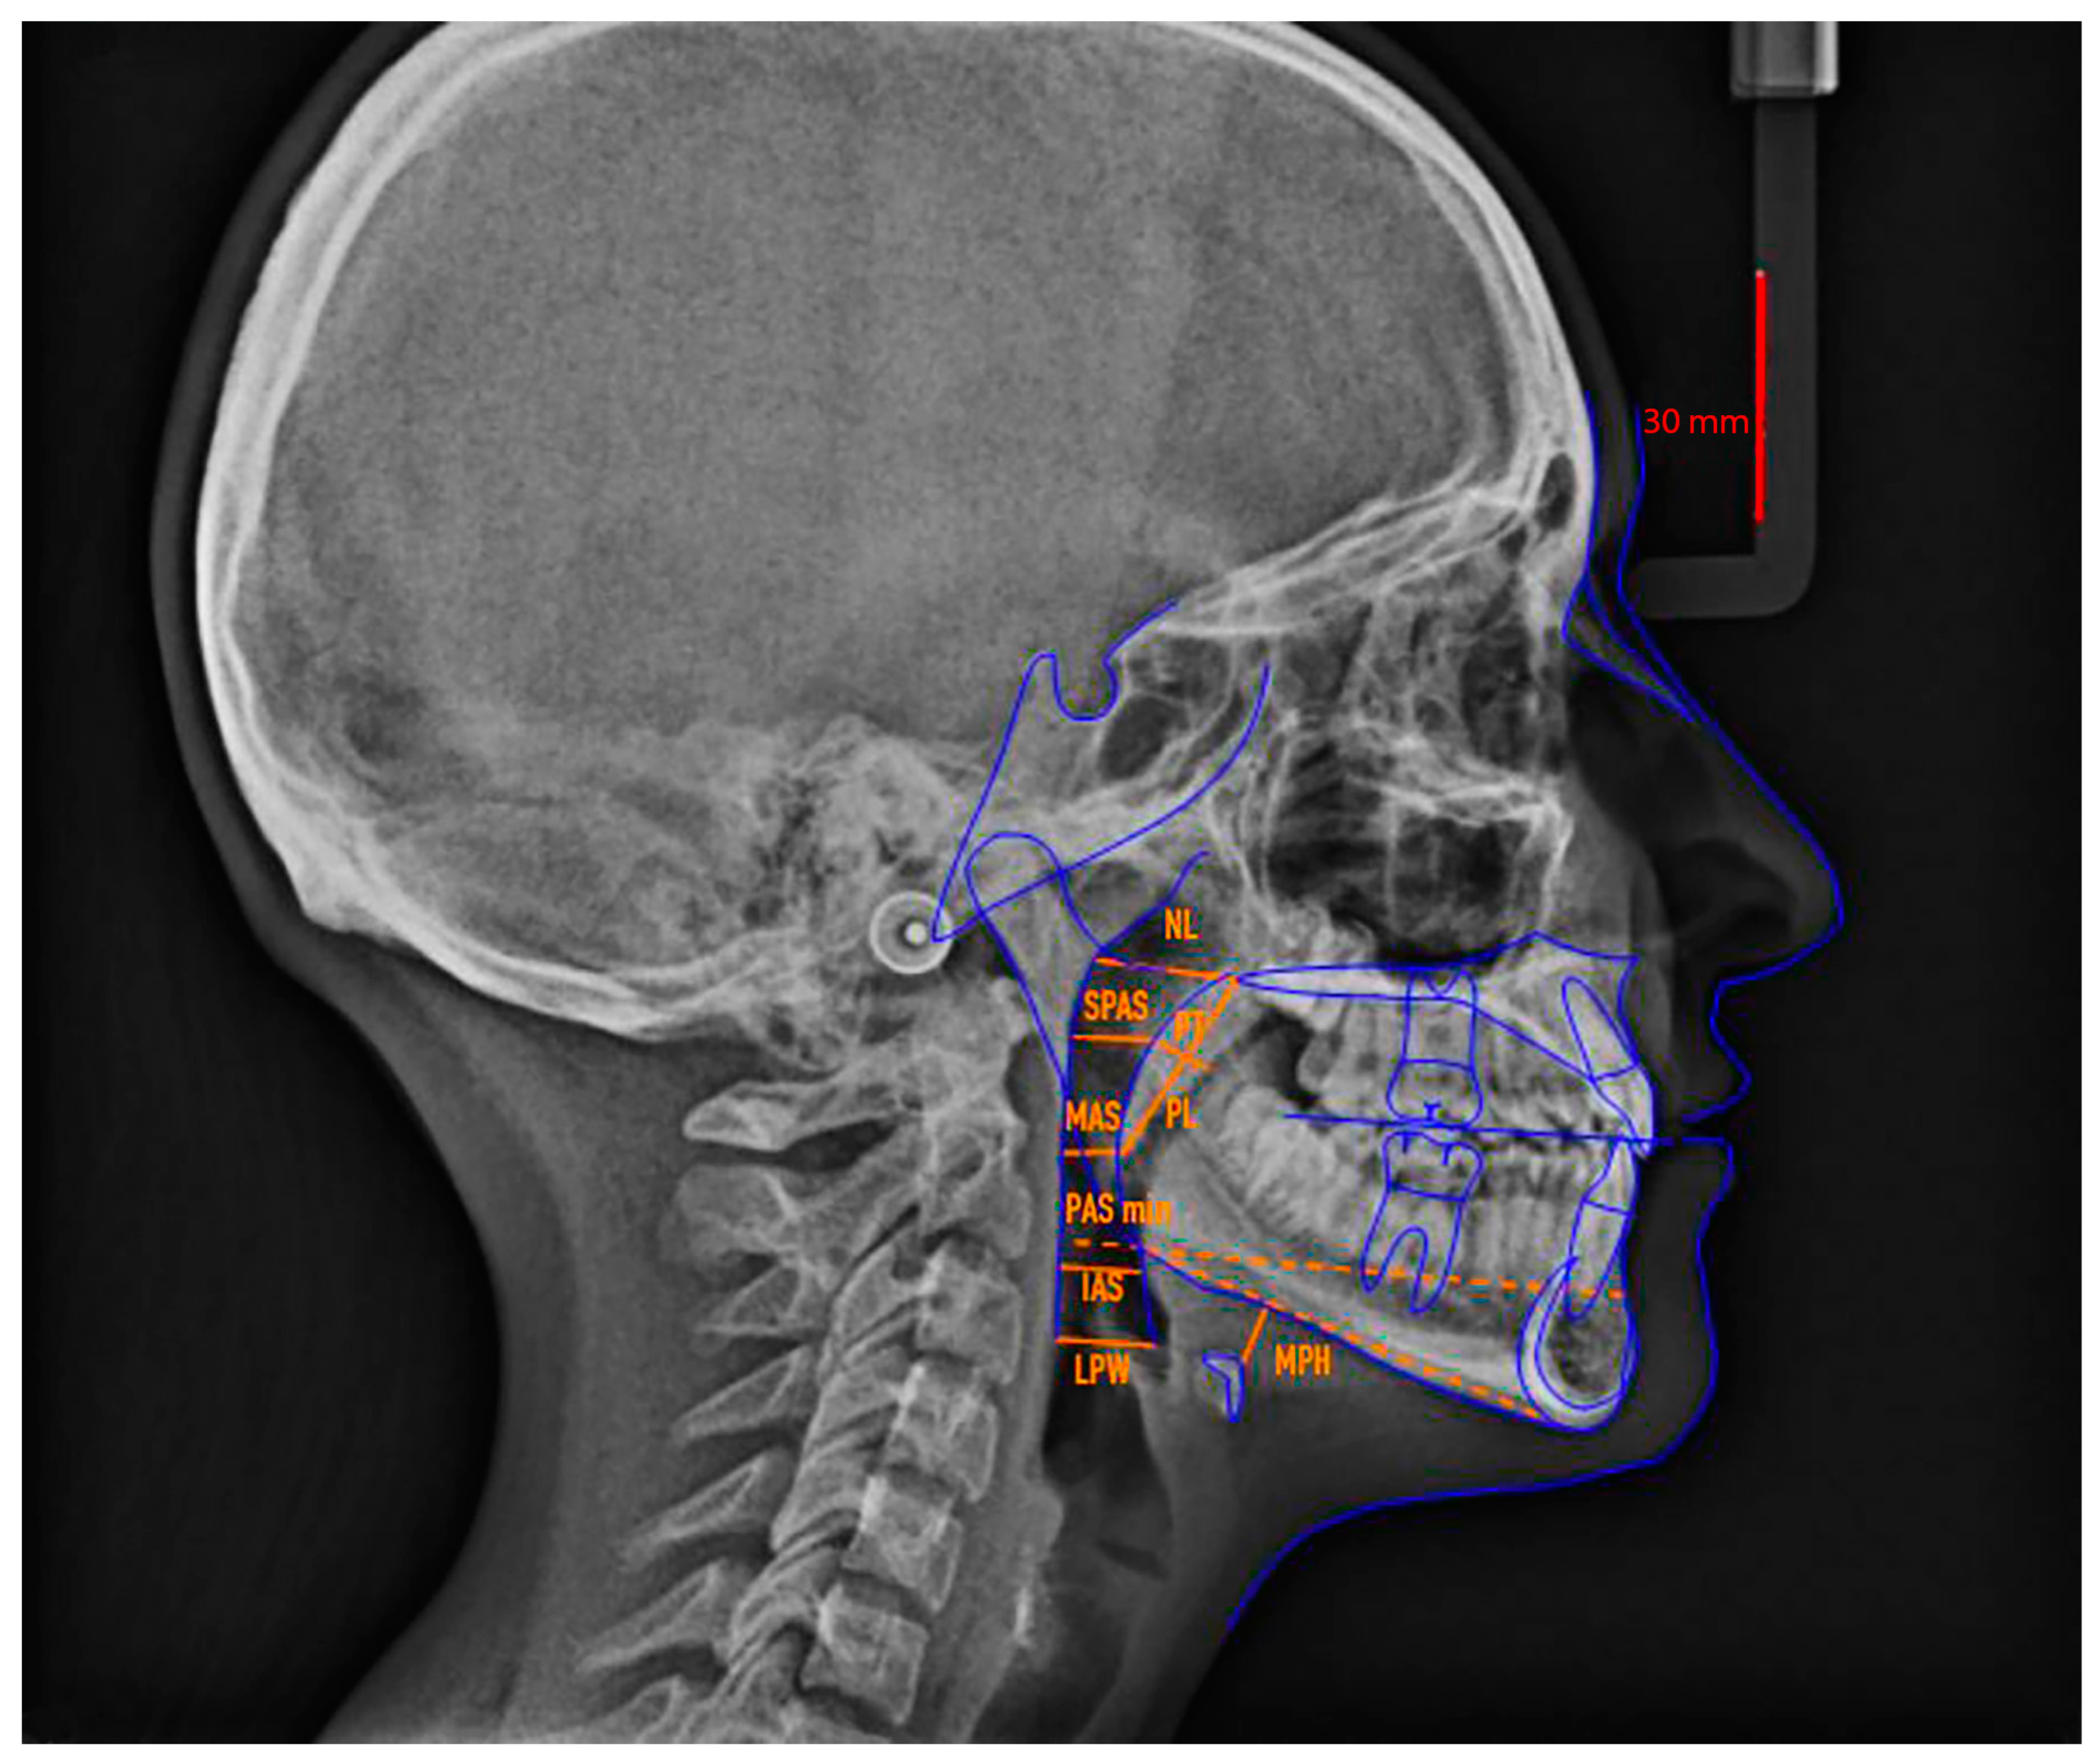

| Points and Measurements (Abbreviations) | Definition |

|---|---|

| Soft palate | |

| MPP | Middle point of the posterior wall of the soft palate |

| MPA | Middle point of the anterior wall of the soft palate |

| PT | Soft palate thickness |

| PL | Soft palate length |

| Nasopharynx | |

| Ad1 | Point at the intersection between the posterior pharyngeal wall and PNS-Ba line |

| NL (nasopharynx length) | Distance between Ad1 and PNS |

| PD (nasopharynx depth) | Line parallel to the bispinal plane and connecting PNS and the posterior margin of pharynx |

| Oropharynx | |

| SPAS (point) | Projection of the MPP point on the pharyngeal wall |

| SPAS | Superior Pharyngeal Airway Space: from half of the posterior border of the soft palate (MMP) perpendicular to the closest point on the posterior wall of the pharynx |

| U1 | Terminal part of the uvula |

| U2 | Projection of the U1 point on the pharyngeal posterior wall |

| MAS | Mean Airway Space: U1—U2 |

| T1 | Intersection of the tongue’s base and the line of point B and Go |

| T2 | T1 projection on the posterior wall of the pharynx along the parallel line Go-B |

| PAS min | Pharyngeal Airway Space minimum: T1—T2 distance along the Go-B parallel line |

| Ph1 | Intersection of the tongue’s base and vallecula of epiglottis |

| Ph2 | Ph1 projection on the posterior wall of the pharynx |

| IAS | Inferior Airway Space: from the superior margin of the epiglottis (Ph1) to the closest perpendicular point on the posterior wall of the pharynx |

| Hypopharynx | |

| Va1 | Base of the epiglottic vallecula |

| Va2 | Va1 projection on the posterior wall of pharynx |

| LPW | Lateral Pharyngeal Wall: distance between the epiglottic vallecula (Va1) and the posterior wall of pharynx perpendicular to Va1 |

| Hyoid bone | |

| H1 | The most cranial point of the body of the hyoid bone |

| H2 | Projection of the H1 point on the perpendicular line of the inferior margin of the jaw (Go—Gn) |

| MPH | Mandibular Plane—Hyoid bone: distance from the most anterior and superior point of the hyoid bone (H1) perpendicular to the mandibular plane |